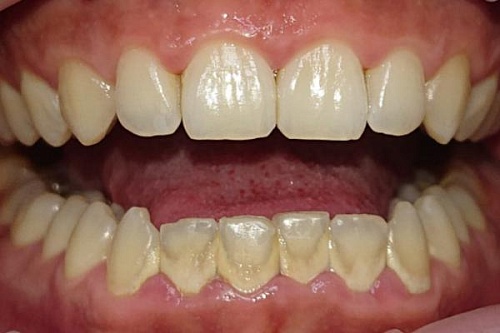

Установка виниров E-max

Пациентка обратилась с жалобой на жёлтый цвет эмали и белые пятна на передних зубах. Из предложенных вариантов лечения пациенткой был выбран самый быстрый и эстетичный — установка керамических виниров E-max.

Установка виниров E-max До

Установка виниров E-max После